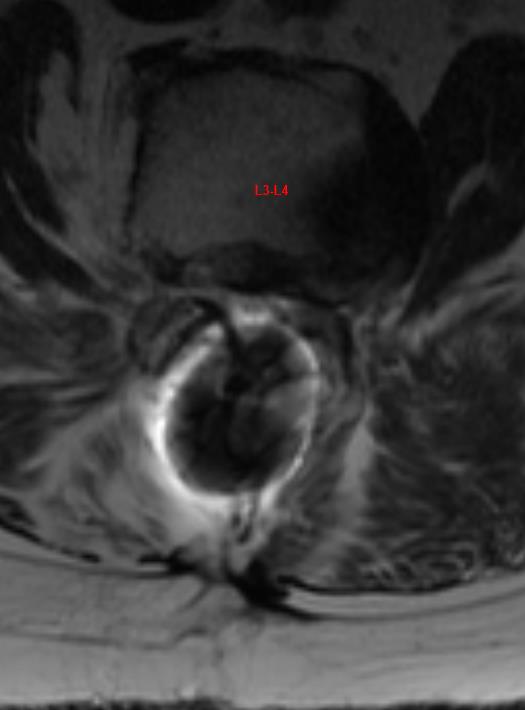

From www.jocn-journal.com

Distant Harrington rod migration 35 years after implantation Journal Harrington Rod Material Since the introduction of the harrington rod in 1962, new rod materials and concepts have been developed. Rigid rod fixation has achieved. It's attached to the spine with the goal of holding it in a straighter position so its vertebrae can't become more. Historically, this rod was implanted along the. A harrington rod for scoliosis is instrumentation used in spinal. Harrington Rod Material.